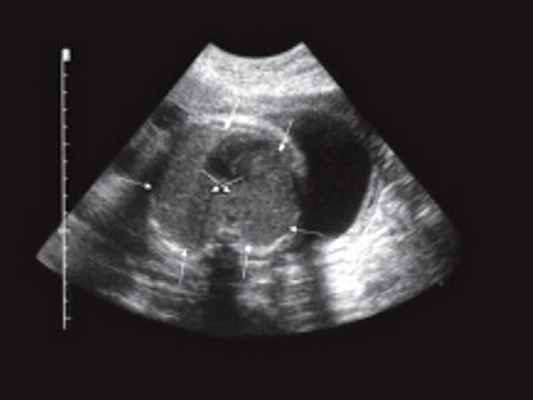

Рис. 2. Эндоректальные ультрасонограммы при контрольном осмотре спустя 1,5 года после начала лечения.

а) На уровне предстательной железы.

На уровне семенных пузырьков.

Спустя 1,5 года после начала терапии при контрольном ТРУЗИ стенки прямой кишки имели обычное строение, элементов опухоли не определялось (рис. 2).